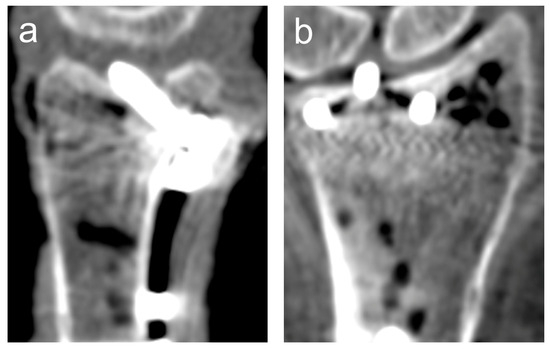

2.4. Intra-Articular Penetration

2.5. Imaging